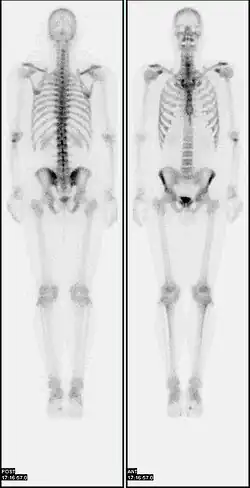

![]() A nuclear medicine whole-body bone scan. The nuclear medicine whole-body bone scan is generally used in evaluations of various bone-related pathology, such as for bone pain, stress fracture, nonmalignant bone lesions, bone infections, or the spread of cancer to the bone. | |

A bone scan or bone scintigraphy /sɪnˈtɪɡrəfi/ is a nuclear medicine imaging technique used to help diagnose and assess different bone diseases. These include cancer of the bone or metastasis, location of bone inflammation and fractures (that may not be visible in traditional X-ray images), and bone infection (osteomyelitis).[1]